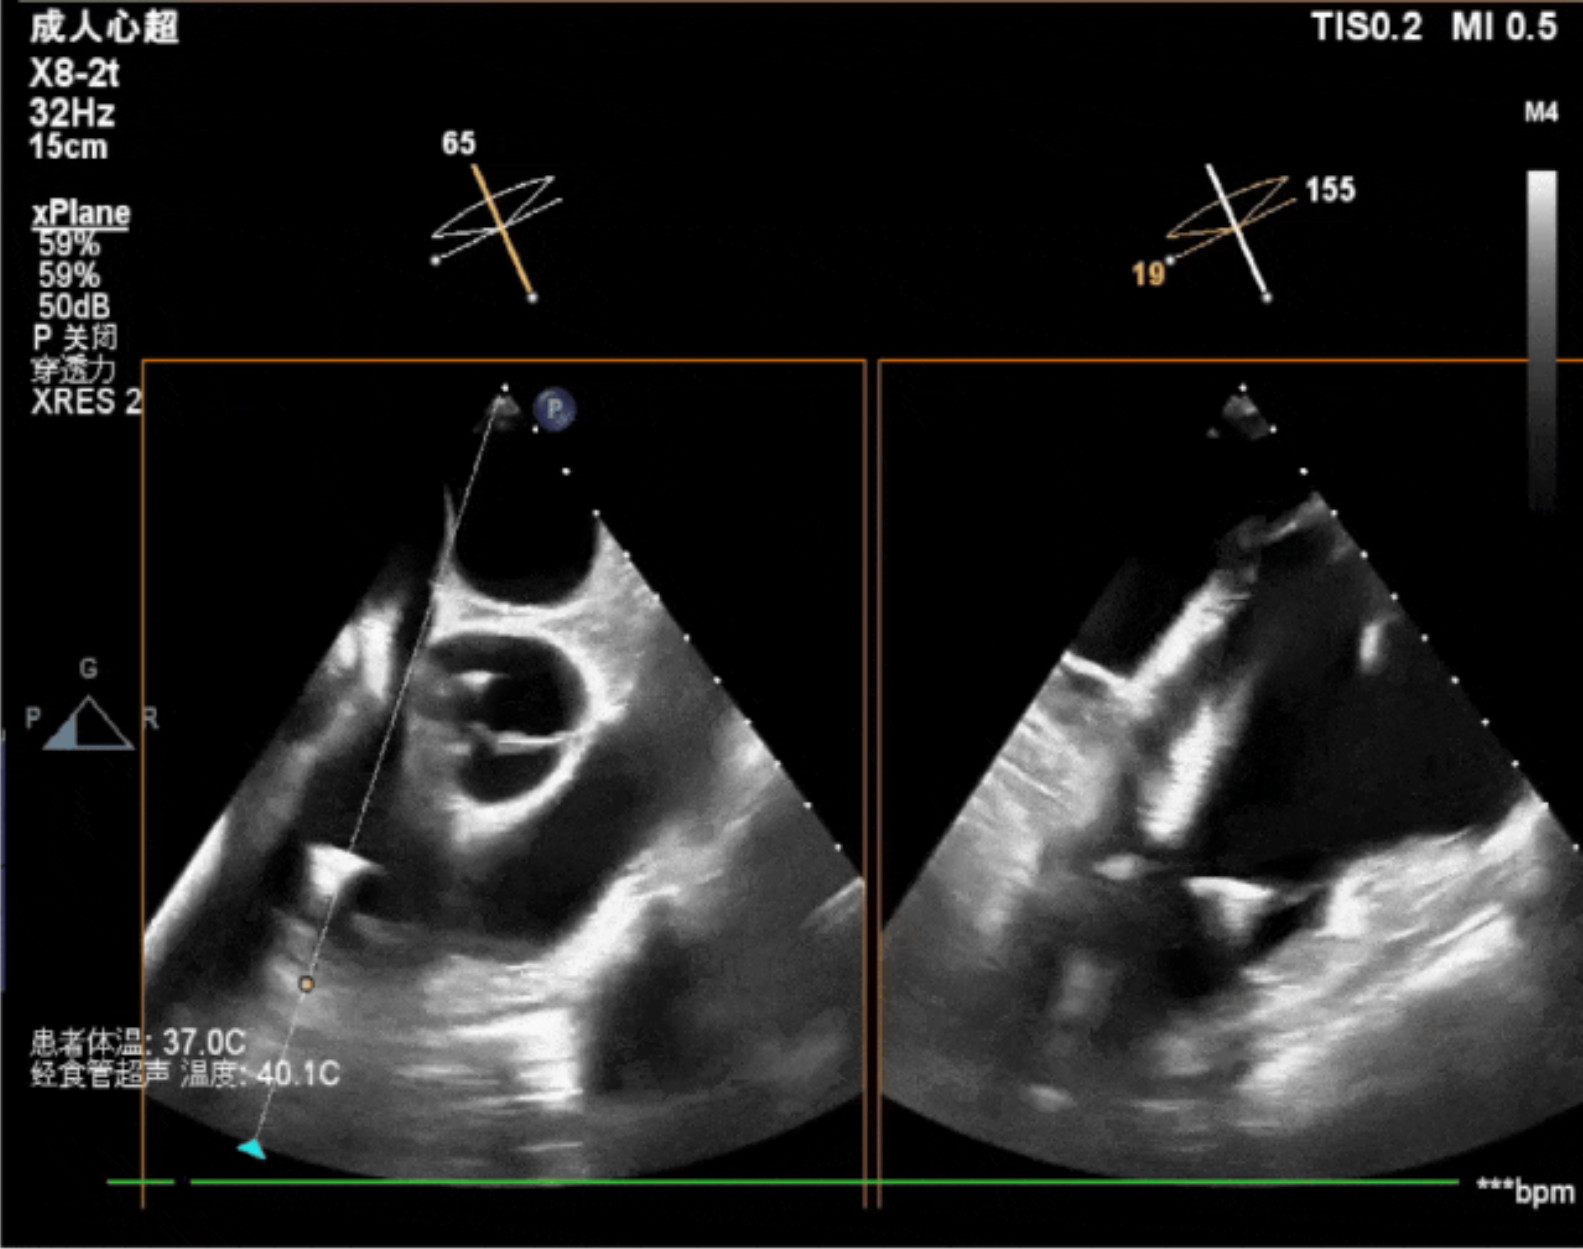

術(shù)中影像

術(shù)中經(jīng)食道超聲輔助下可見LuX-Valve Plus夾持件抓捕瓣葉狀態(tài)良好,夾持件在位,室間隔錨定位置良好,假體瓣膜整體錨定狀態(tài)穩(wěn)固。

術(shù)后即刻經(jīng)食道超聲可見,三尖瓣假體瓣膜位置合適,牛心包瓣葉運動狀態(tài)良好,開閉正常,瓣周及瓣葉對合緣處未見明顯返流,心電圖及心包狀態(tài)較術(shù)前無明顯變化。